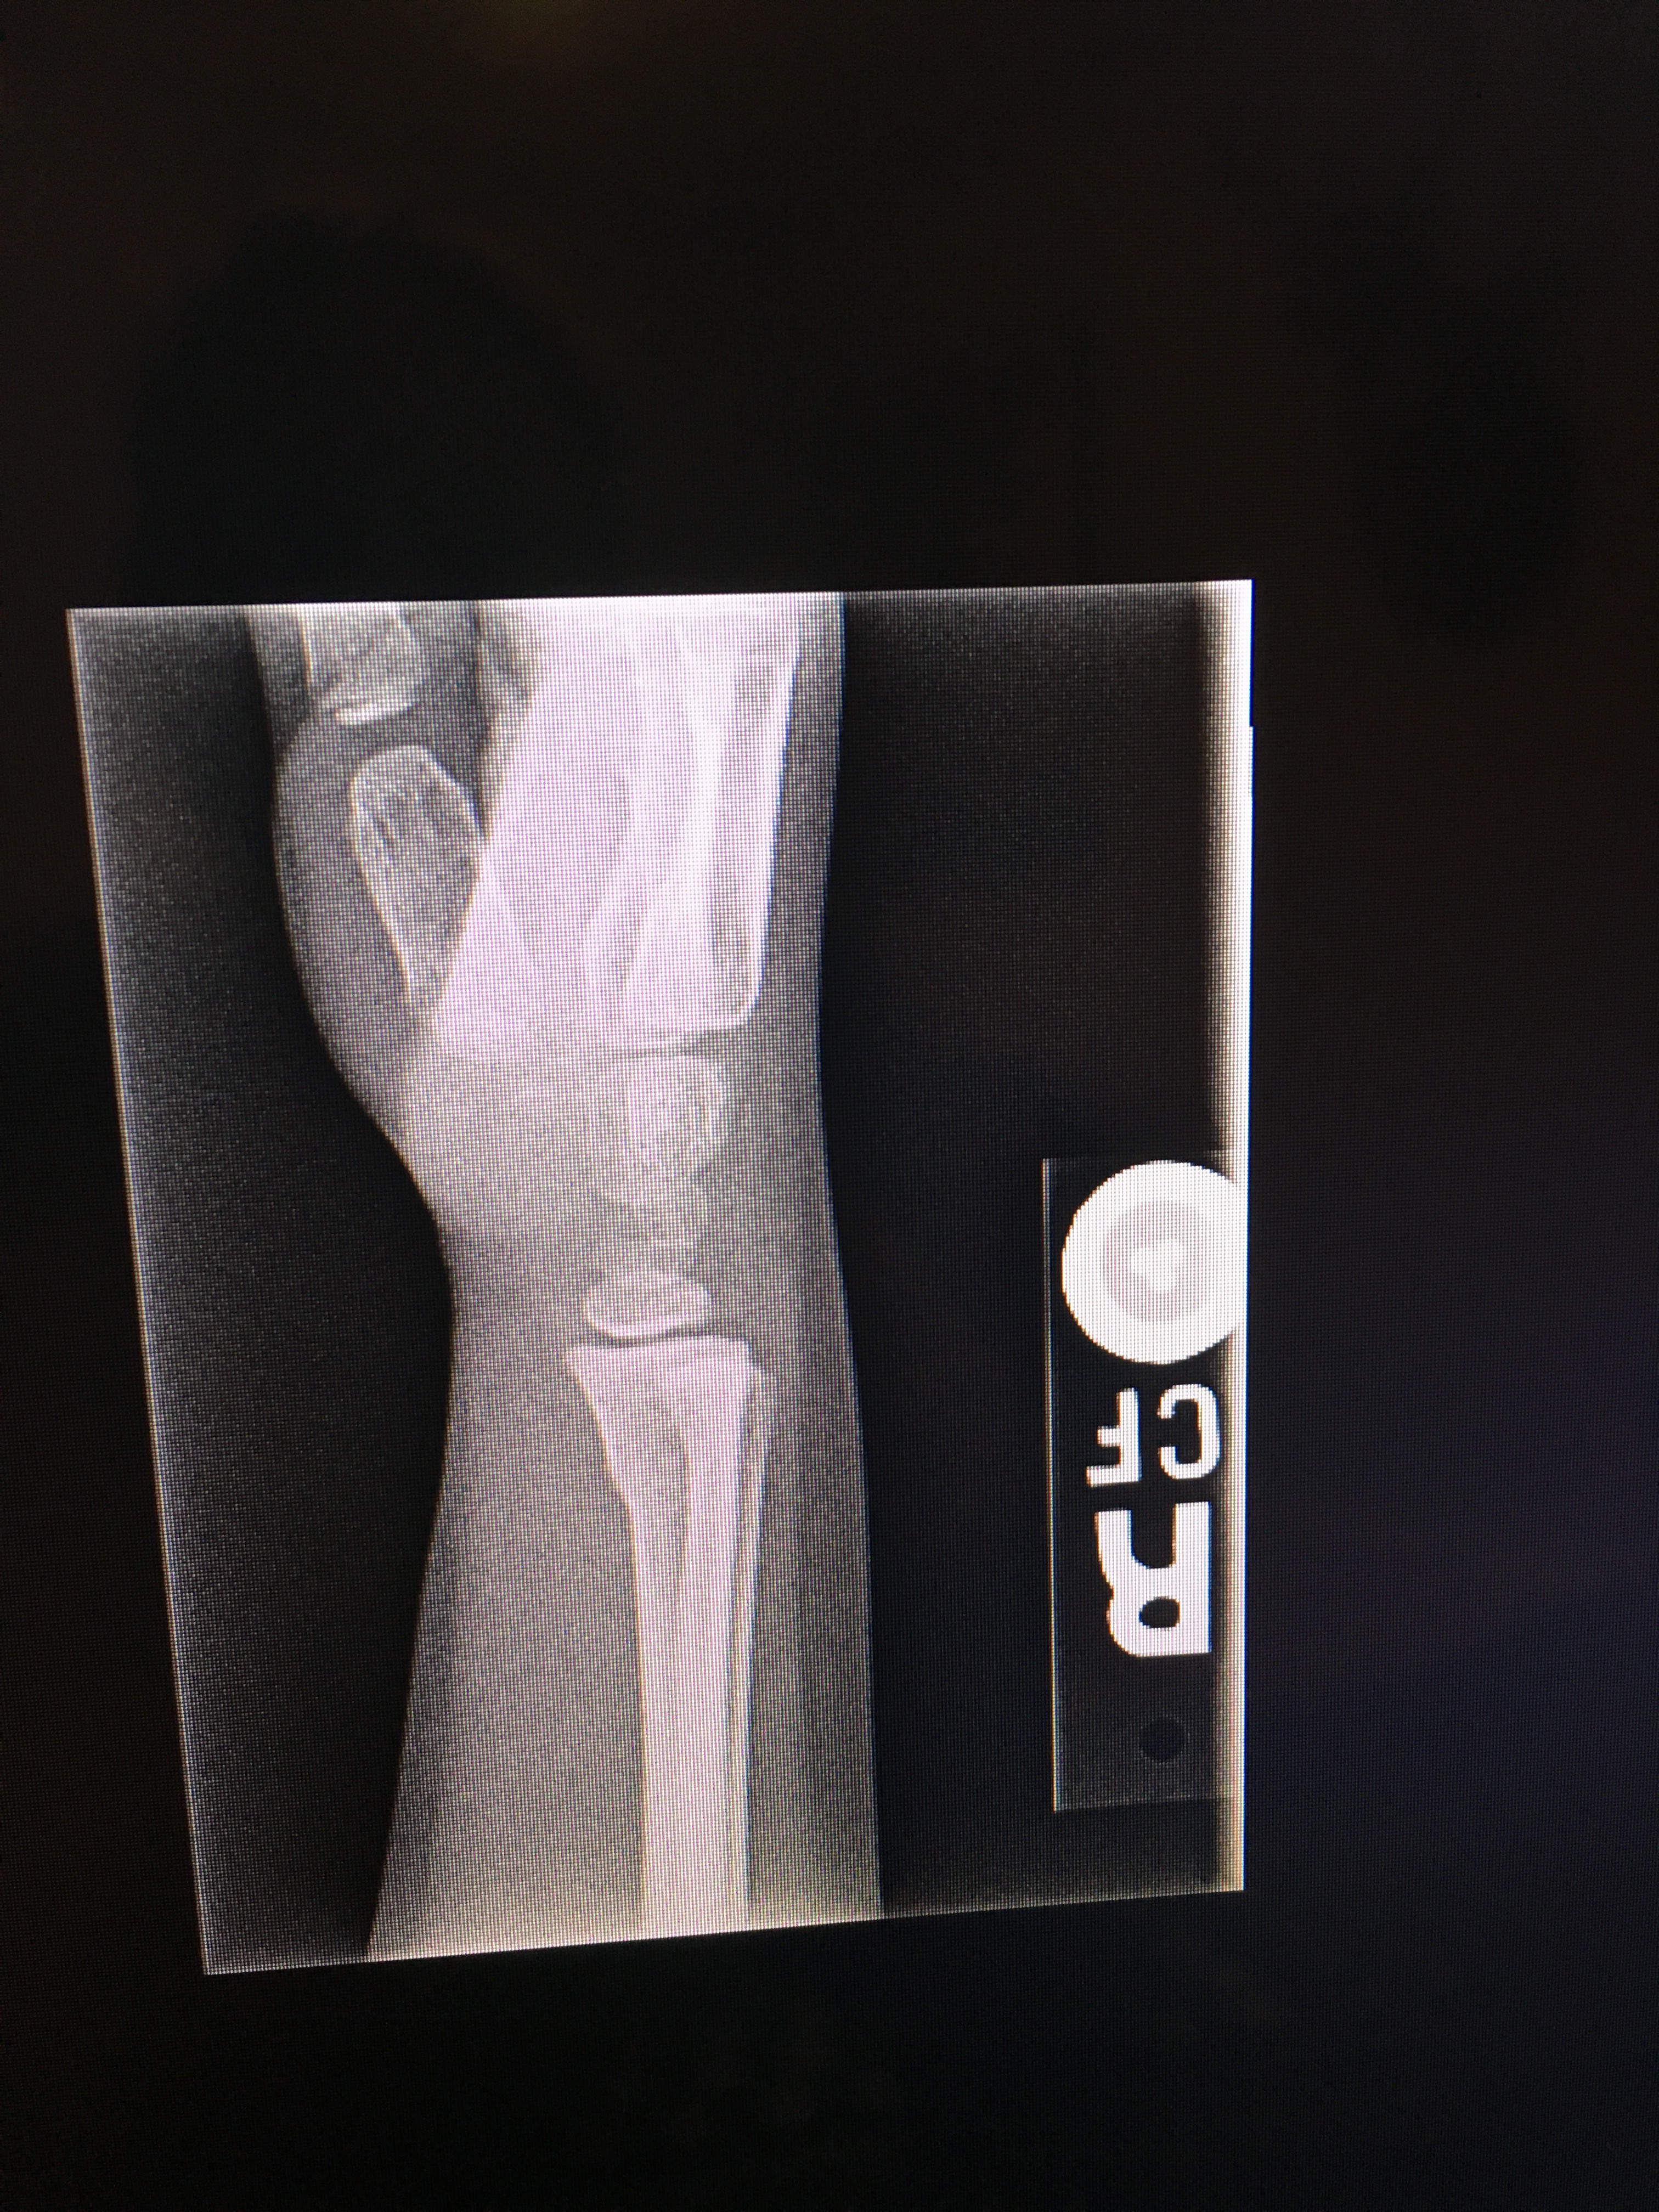

Her wrist did end up being a slight buckle fracture. I was glad I decided to take her in. You can’t really even tell unless you know what you’re looking for in the X-ray.

Next step, a follow-up appointment with the Ortho. So much for “cheap entertainment.” I feel fortunate. Her fall down the stairs could have been much worse.